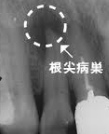

「歯根嚢胞」(しこんのうほう)について。

羽曳野市の加藤歯科です。 今回は「歯根嚢胞」についてです。 一般に歯の周囲はあごの骨で覆われています。 この歯の根の先端部分の骨に膿の袋がで